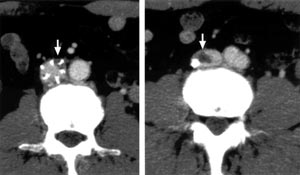

| Fig. 4 Postoperative enhanced computed tomography. →:

intravenous thrombus entrapped by temporary IVC filter |